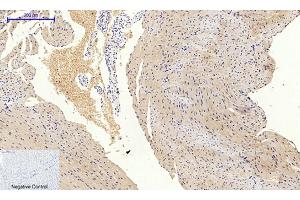

L’anticorps anti-PIK3R1 Monoclonal Souris est utilisé pour la détection de PIK3R1 dans des échantillons de Humain, Souris et Rat. Il a été validé pour WB, IF et IP.

This antibody reacts with p85alpha, which is regulatory subunit of PI3-kinase on Western blot, Immunoprecipitation and Immunocytochemistry. This antibody recognizes mutant p85alpha protein expressed in E. coli to be possessed in amino acid position '1-79' described below. This antibody does not react with p85beta.